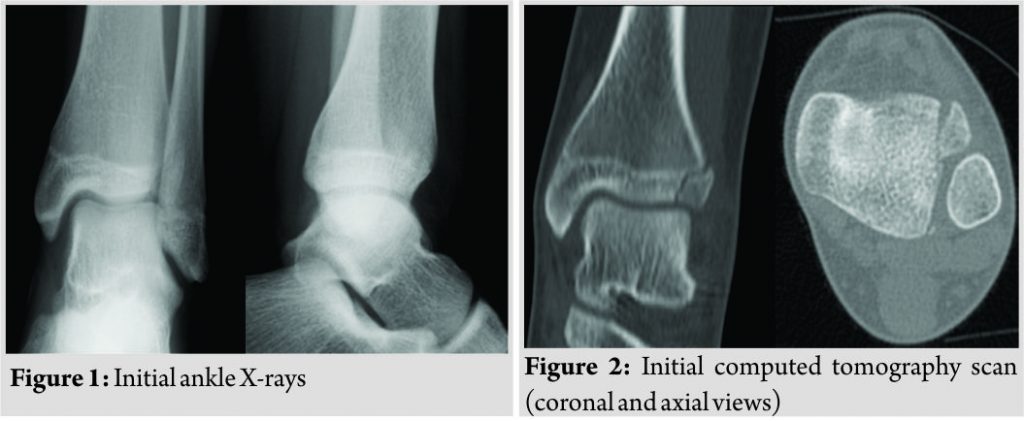

A 13-year-old female competitive basketball player sustained a forced external rotation type of injury to her left ankle while training. The injury was initially diagnosed as a mild ankle sprain by her clubs physician who recommended 2weeks non weight-bearing, followed by a period of progressive return to sports. No imaging studies were performed at that time. Due to persistent moderate ankle pain and inability to perform, the patient was referred to our orthopedic department 2months after the initial injury. She had mild swelling over her ankle and well-localized pain on palpation of the anterolateral portion of her ankle. Weight-bearing was painful but the range of motion was normal, and there were no palpable bony deformity, bruising, or neurovascular compromise. Plain radiographs showed an irregular lucency on her lateral distal tibial epiphysis (Fig. 1) that was further evaluated with a computed tomography (CT) scan – the coronal and axial images showed a small, Salter-Harris Type III fracture of the anterolateral portion of the distal tibial epiphysis (Fig. 2),

findings consistent with the diagnosis of a juvenile Tillaux Fracture. Non-operative treatment was decided as the fracture was considered undisplaced (even though in hindsight slight rotation of the fragment was noticeable on the CT scan). The treatment consisted of 6 weeks of immobilization in a plaster splint followed by progressive physical therapy and rehabilitation. This course of treatment was unsuccessful, as 6 months after the initial injury, the patient still had pain on weight-bearing and was unable to return to sports. At this time, another CT scan was performed that showed a lucency between the fragments and sclerosis of the fracture borders, consistent with nonunion of the fracture and surgical treatment was proposed (Fig. 3).